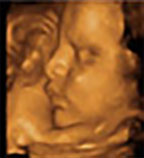

怎样选择排畸时间?| 仪器 | 美国E8四维 | 普通四维 |

![]() |

| 画质 | 立体动态成像,画质比较清晰 | 动态成像画质普通 |

| 优势 | 多方位、角度地观察孕宝宝的生长发育,对孕妇潜藏的疾病进行检测,无辐射。 | 较准确地动态呈现腹中胎儿的生长发育情况 |

| 劣势 | 目前影像科分辨率高的 | 清晰度稍差,数据分析能力较弱 |